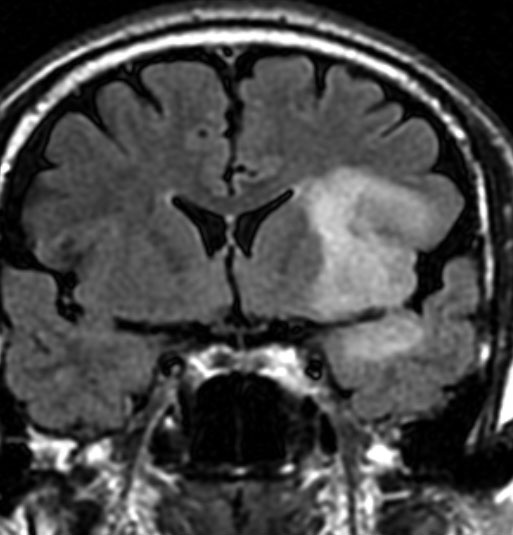

診断 MRI

• MRI-T1強調画像では低信号となり,T2強調画像とフレア画像では高信号域となります

• グリオーマの中では,T2強調画像での腫瘍内部のコントラストが強く,石灰化の部分は強い低信号域として,のう胞は均一な強い高信号域となります

• 周囲脳組織浮腫あるいは腫瘍浸潤部は淡い高信号域として描出されます

• 脳浮腫を伴うものはグレード3の可能性が高いです

• ガドリニウムによる造影では,悪性度が高くなるにつれて部分的な増強像が増えます

MRI画像ではびまん性星細胞腫と区別がつかないものがあります

左は脳ドックで発見された時のMRIです。壮年男性で無症状でしたので経過観察をしました。fronto-insulo-temporal gliomaと呼ばれる腫瘍で,びまん性星細胞腫と区別がつきません。右は無治療で6年後の画像です。ごくわずかに増大していますが,患者さんは相変わらず無症状で普通に働いています。このように数年間経過を見ても問題ない例もありますし,逆に数ヶ月で顕著な増大傾向を示すものもあります。発見されたらまずは,MRIを2ヶ月くらいで繰り返してどのくらいの速さで進行するかどうかをみるのが大切です。